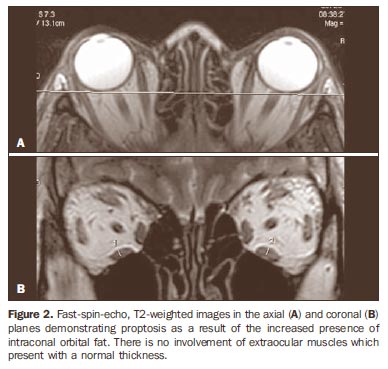

Exophthalmos может быть любой двусторонним (оба глаза выпирают) или односторонний (всего, один глаз выпирает). Врачи используют экзофтальмометр, чтобы измерить степень exophthalmos. …